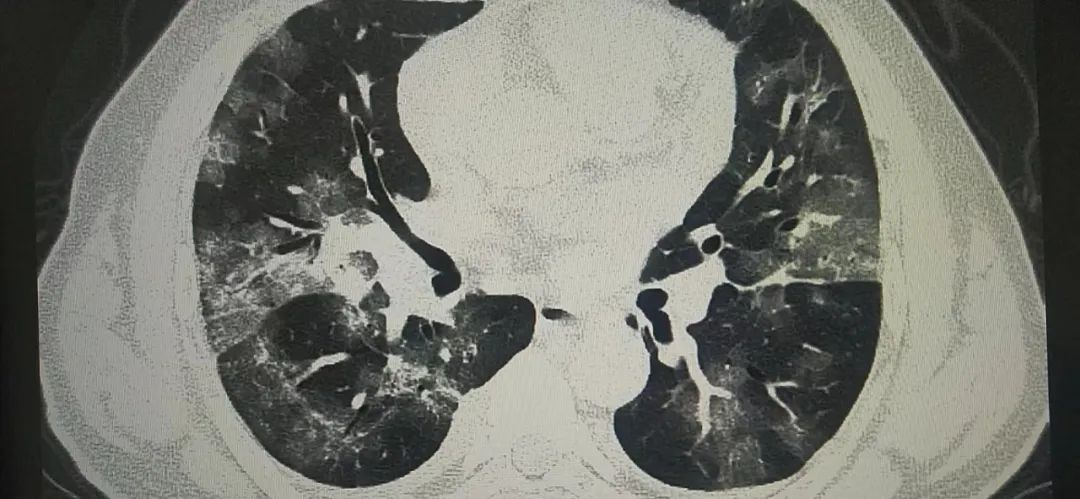

胸片只能做一个初步的粗略判断,付建英介绍,胸部CT则以1毫米为一层的断面,精准展现患者的肺部影像,就连软组织、骨骼场都能看得一清二楚,细微病灶也不会漏诊。在高分辨率的大尺寸屏幕上分析患者CT,即使是较小的磨玻璃样结节,都逃不过胸部CT的慧眼。

据陕西冶金医院医学影像科付建英主任讲,目前新闻各种报道奥密克戎感染后大部分为无症状或轻症,我自己接诊的患者中一部分有出现肺部表现的患者。比如上面的病例,CT检查都是出现了肺部表现,一个人是病变局限,病变于胸膜下分布。表现为单发或多发磨玻璃样密度结节状、斑片状影。其内可见空气支气管征和血管增粗表现。另外一个则是弥漫性磨玻璃样渗出,病变进展,病灶增多、范围扩大。可累及多个肺叶,下叶居多。病灶变密实。严格意义上讲,这几个病例都倾向于类似于新冠感染后的肺部表现。随着感染人数增多,可能还会有类似的病例出现。好在这样的病例确实不多,大部分还是上呼吸道感染的症状居多,发热咽痛是最常见的症状表现,但如果出现呼吸困难,还是要到医院拍个CT的。